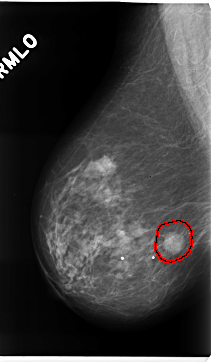

FILE: C_0226_1.LEFT_CC.OVERLAY

TOTAL_ABNORMALITIES 1

ABNORMALITY 1

LESION_TYPE CALCIFICATION TYPE AMORPHOUS DISTRIBUTION CLUSTERED

ASSESSMENT 3

SUBTLETY 3

PATHOLOGY BENIGN

TOTAL_OUTLINES 1

BOUNDARY